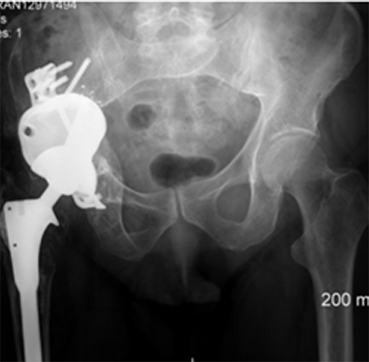

This case involves a 67-year-old gentleman who faced a series of complications due to hip trauma he had experienced over 50 years ago. After his primary and revision surgeries, and subsequent three hip replacements, he was left with a failing hip implant. His most recent hip replacement lasted 13 years before massive circumferential acetabular osteolysis caused the cup to loosen. Imaging revealed anterior and medial wall deficiencies, while the posterior column remained intact. The patient had a metal-on-polyethylene (MoP) bearing, which over time led to the wear of the polyethylene liner, triggering an inflammatory reaction and bone loss due to polyethylene debris.

The surgical plan required a custom 3D-printed acetabular cup, designed specifically for the patient's anatomy. The implant was designed with three flanges for optimal fixation. The surgery involved a posterior approach, with meticulous bone preparation to minimize further bone loss and ensure the custom implant fit securely.

This case represents ALTR with MoP. ALTR was characterized by massive osteolysis of the pelvic bone, which was most likely caused by polyethylene wear debris. This case underscores the complexity of revision hip surgeries and highlights the value of custom 3D-printed implants for achieving secure fixation and improving patient outcomes despite significant bone loss. Update at 7 years post operative is that the patient has excellent hip function and more can be seen in this paper:

Durand‐Hill, M., Henckel, J., Di Laura, A., & Hart, A. J. (2020). Can custom 3D printed implants successfully reconstruct massive acetabular defects? A 3D‐CT assessment. Journal of Orthopaedic Research®, 38(12), 2640-2648.5.https://doi.org/10.1002/jor.24752